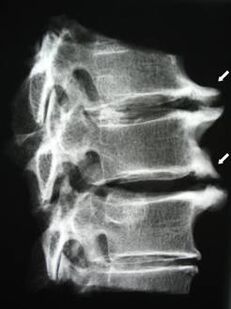

In de beginfase wordt osteochondrose gedetecteerd met behulp van MRI. Later kan pathologie worden gediagnosticeerd met behulp van radiografie. Op röntgenfoto's van de cervicale wervelkolom worden een afname van de afstand tussen de wervels, pathologische veranderingen in de facetgewrichten en osteofytose merkbaar.